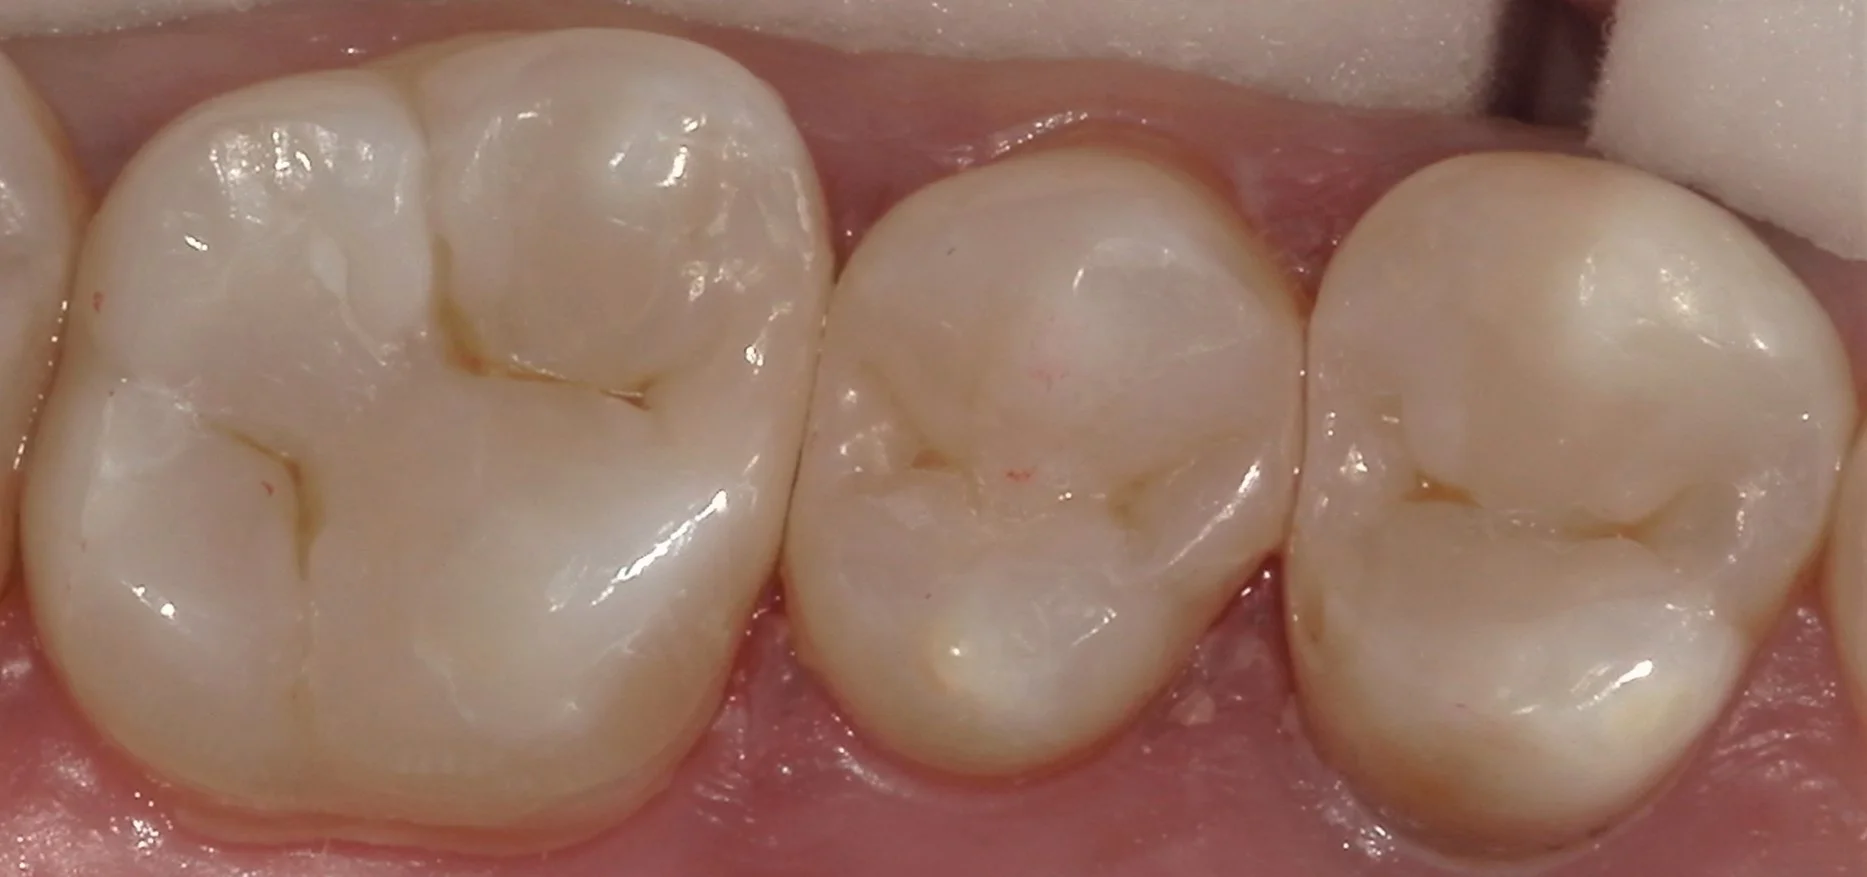

そして詰め終わったのが、こちらです。

随分と自然な形に仕上げられたかと思います。

そして詰め終わったのが、こちらになります。

段差もなく綺麗に詰めることが出来ましたヽ(゚∀゚)ノ パッ☆

あとはこれが1年でも長持ちしてくれることを祈るだけですね!

術前術後はこんな感じです。

自然に綺麗に仕上げられたかと思います!